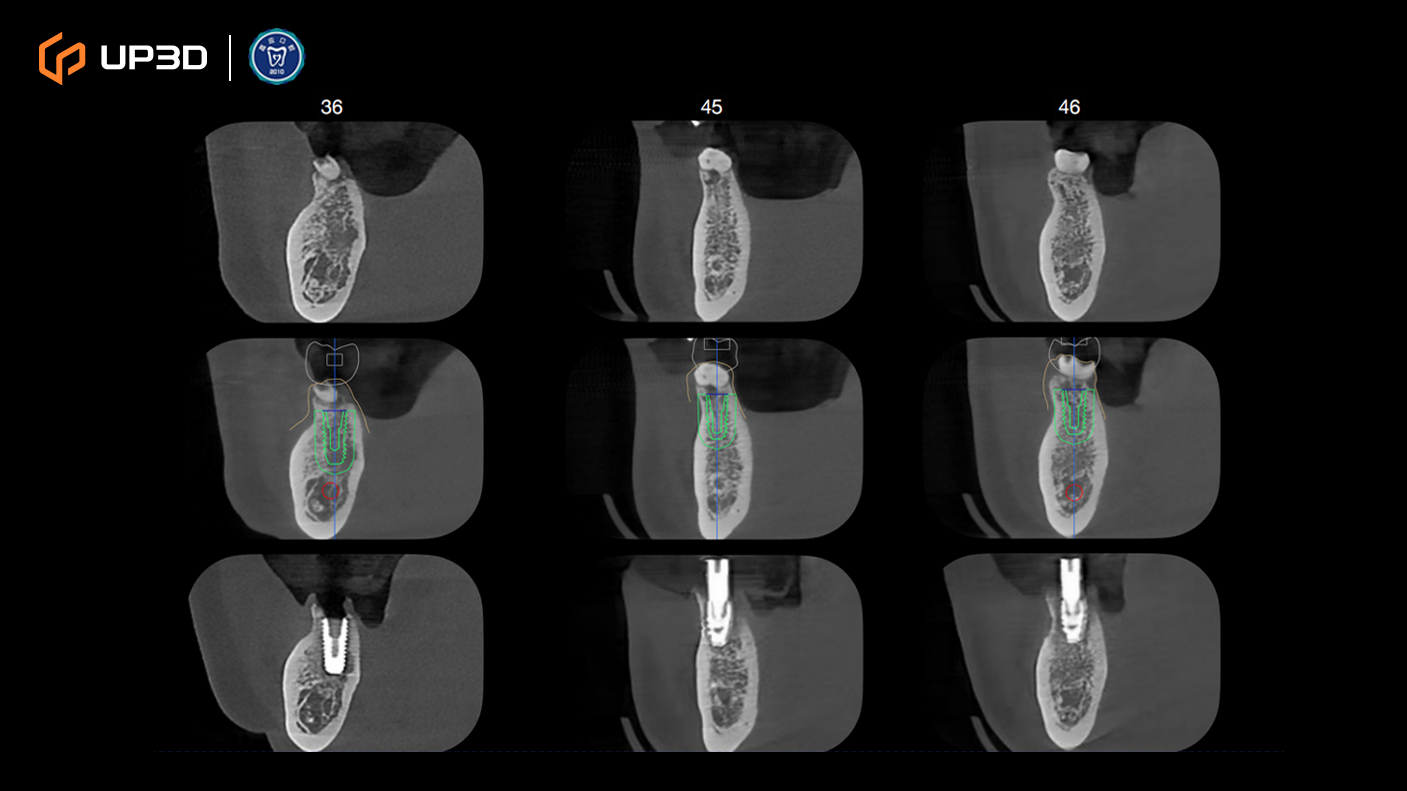

2.3 Radiographic Assessment

A panoramic radiograph and cone-beam computed tomography (CBCT) revealed multiple missing teeth and uneven alveolar ridge resorption, with moderate-to-limited bone volume in selected areas. Based on measurement and analysis, implant placement was planned at sites including 16, 14, 12, 21, 24, 26, 36, 45, and 46 (FDI tooth numbering).

Intraoral scan data were merged with CBCT to complete a 3D implant plan:

Six implants planned in the maxilla and three implants in the mandible

Surgical guide (guided surgery) pathways were planned digitally

Digital tooth setup and guide fabrication supported accurate positioning and a minimally invasive approach

Guided surgery helped improve consistency in implant angulation and depth control, supporting a stable foundation for immediate loading.